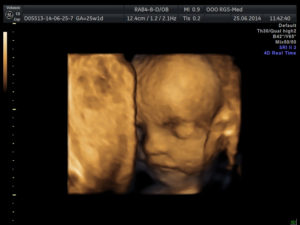

3Д УЗИ делается при беременности с целью детального просмотра частей тела, черт лица плода. При исследовании на экран ультразвукового устройства передается объемное голографическое изображение.

Трехмерное сканирование плода при беременности дает возможность в объемном виде оценить состояние ребенка. Картинка передается на экран аппарата в цветном режиме. Чаще метод используют на втором плановом скрининге, когда четко видны части тела плода.

С помощью 3Д УЗИ делают фотографии и видеозапись движений ребенка в утробе матери. В редких случаях просмотреть малыша не удается из-за того, что он поворачивается спиной. Тогда диагностика проводится через 15–20 минут.

Трехмерное изображение представляется в 3 измерениях — глубине, высоте и ширине. Беременная может увидеть ребенка на экране УЗИ-аппарата в цвете. При этом детально просматривается каждая часть лица и тела, мимика плода.

У него неплохо выражены черты лица. Проводимое 3D-УЗИ в 25 недель позволит увидеть то, как будет выглядеть маленький человек, когда родится. Глаза еще закрыты, брови только начали развиваться, рот сформировался. Продолжает развиваться ушная раковина.